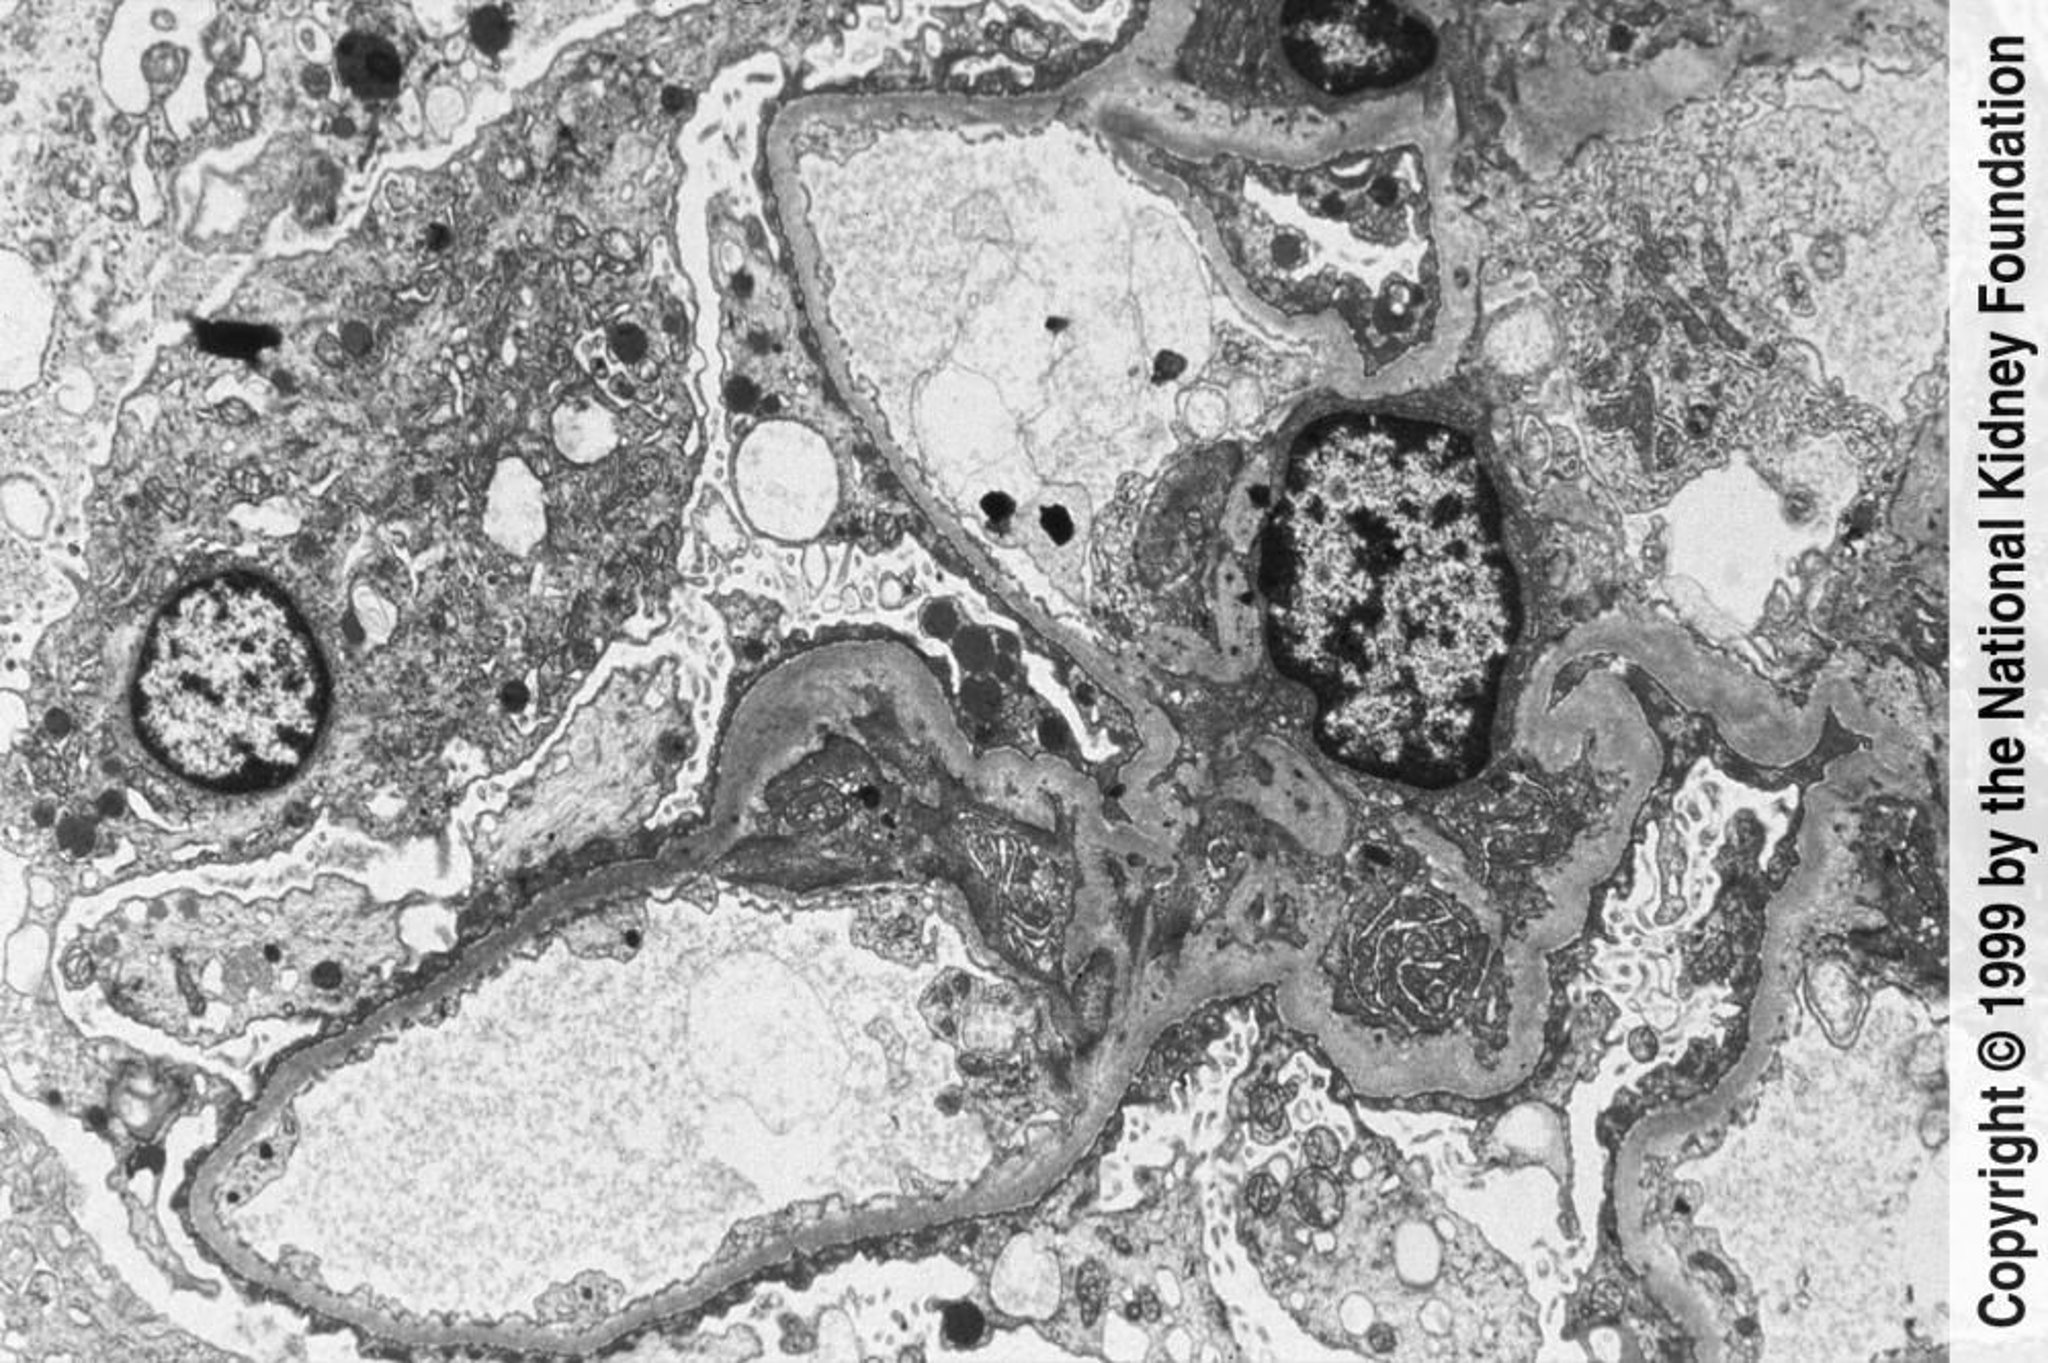

巣状分節性糸球体硬化症(足突起の鈍化および消失)

透過型電子顕微鏡下で足突起の広範な鈍化および消失が認められる(3000倍)。

Image provided by Agnes Fogo, MD, and the American Journal of Kidney Diseases' Atlas of Renal Pathology (see www.ajkd.org).